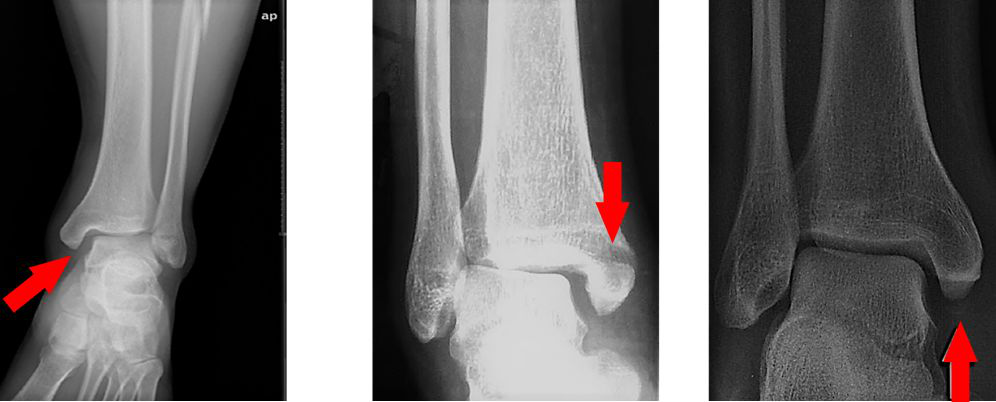

影像学检查

· X 片踝关节正侧位踝关节呈后脱位,见腓骨远端骨折,近端骨折块后内侧移位,交锁于胫骨后方外侧棘,侧位可见接近于正位相;